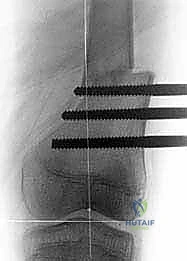

* إصلاح الفخذ الأفحج (Coxa Vara Correction): يقوم الدكتور هطيف بقطع عظمي دقيق في أعلى الفخذ لتعديل الزاوية بين العنق والجسم، وتثبيتها بشرائح ومسامير خاصة بالأطفال. هذا يعيد الشد الطبيعي للعضلات المبعدة ويقضي على العرج.

* المسامير النخاعية المغناطيسية (Magnetic Internal Nails): في حالات معينة للأطفال الأكبر سناً، يمكن استخدام مسامير تزرع داخل العظم وتستطيل عن بعد باستخدام جهاز مغناطيسي خارجي، مما يقلل من خطر العدوى ويوفر راحة أكبر للمريض.